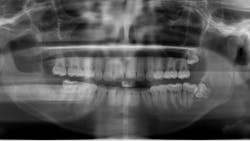

A 14-year-old female presented to her general dentist complaining of pain in the right posterior mandible and mobility of tooth no. 31. Her medical history was otherwise unremarkable. A panoramic radiograph revealed a large, multilocular radiolucent lesion within the entire ramus and posterior body of the right mandible. Tooth no. 32 was within the lesion. Cortical expansion in the area of the lesion was notable. All adjacent teeth were vital. A panoramic radiograph taken at the completion of orthodontic treatment 18 months previously showed no evidence of the lesion.